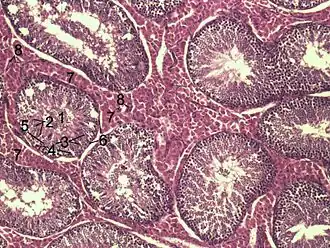

![]() Гистологический срез тестикулярной паренхимы кабана. 1 полость семенного канальца 2 – сперматиды, 3 — сперматициты, 4 — сперматогонии, 5 — клетки Сертоли, 6 — миофибробласты, 7 — клетки Лейдига, 8 — капилляры | |

Поперечное сечение семенного канальца крысы (x250)